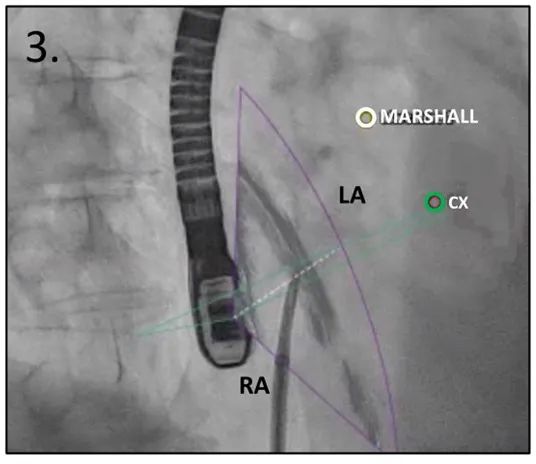

当针头固定到位时,在右前斜(RAO)约30°投照,查看帐篷的方向,这里左心耳开口的标记物没有重叠,可以识别它们的正确轨迹。穿刺位点的部分错位可以通过稍微顺时针或逆时针转动穿刺针,校正高度或后部。

图3:RAO投照中的TSP:白色(Marshell韧带)和绿色(CX)标记表示LAA开口

缩写注释:Ao: 主动脉;CX,左回旋动脉;LA: 左心房;LAA: 左心耳;RA: 右心房;SP: 原发隔;SS: 继发隔;SVC: 上腔静脉;TEE: 经食管超声心动图;TSP: 经房间隔穿刺;白或黑色箭头,卵圆窝处的房间隔。